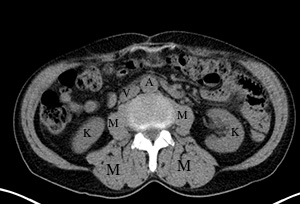

Early IV contrast-aorta (A) is very white, much whiter than muscle (M), and kidneys (K) are also very white around their edges, with darker grey centrally. The major lower body vein, the inferior vena cava (V) is not yet white, and is the same color as muscle. |